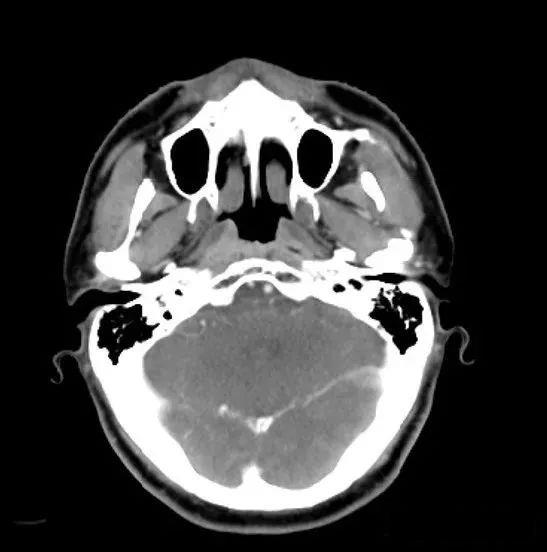

鼻咽癌临床试验,即将在美国上市的中国国产鼻咽癌免疫治疗(PD-1)新药派安普利单抗(Penpulimab、AK105)临床试验正在招募患者这是一个属于靶向治疗的时代,这是一个属于免疫治疗的时代。这是一个新药井喷的时代,也是一旦把握住临床试验的机会,就能创造“奇迹”的时代。自2017年中国正式成为ICH成员之后,我国的临床试验项目数量、尤其是其中Ⅰ期新药临床试